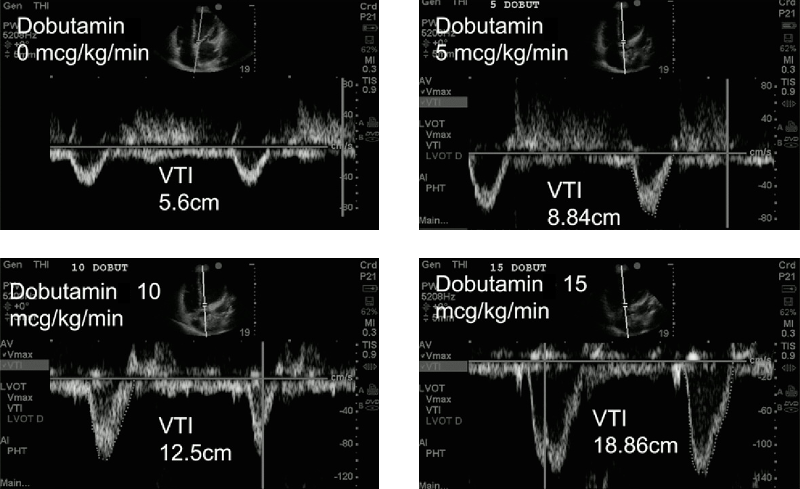

erweiterte Therapiesteuerung anhand der VTILVOT

• Gabe von Dobutamin, 3 min. später Kontrolle der VTI und ggf. weiterer Steigerung des Dobutamins

Therapiesteuerung_VTI

... wie geht es weiter?